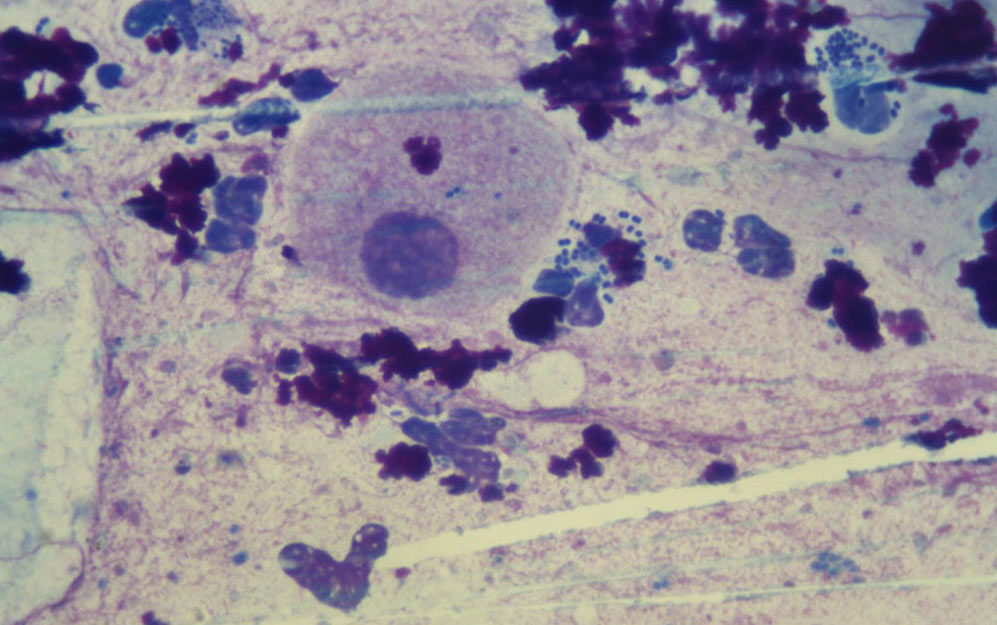

Диплококки — это бактерии сферической формы. Они относятся к семейству Lactobacteriaceae. Представляют собой организмы, соединенные попарно и в редких случаях образующие цепочки. Как известно, различают 2 вида бактерий — грамположительные и грамотрицательные. Диплококки относятся к обоим из них. В медицине выделяют более 80 типов диплококков. Бактерия опасна тем, что является возбудителем воспаления легких, менингита, гонореи. В большинстве случаев диплококки в мазке у мужчины позволяют диагностировать именно гонорею.

Гонококки, которые являются непосредственными возбудителями гонореи у мужчин и женщин. Кроме того, именно гонококки являются самыми патогенными из всех разновидностей диплококков. Этот вид бактерий можно определить только по мазку и высокому числу лейкоцитов.